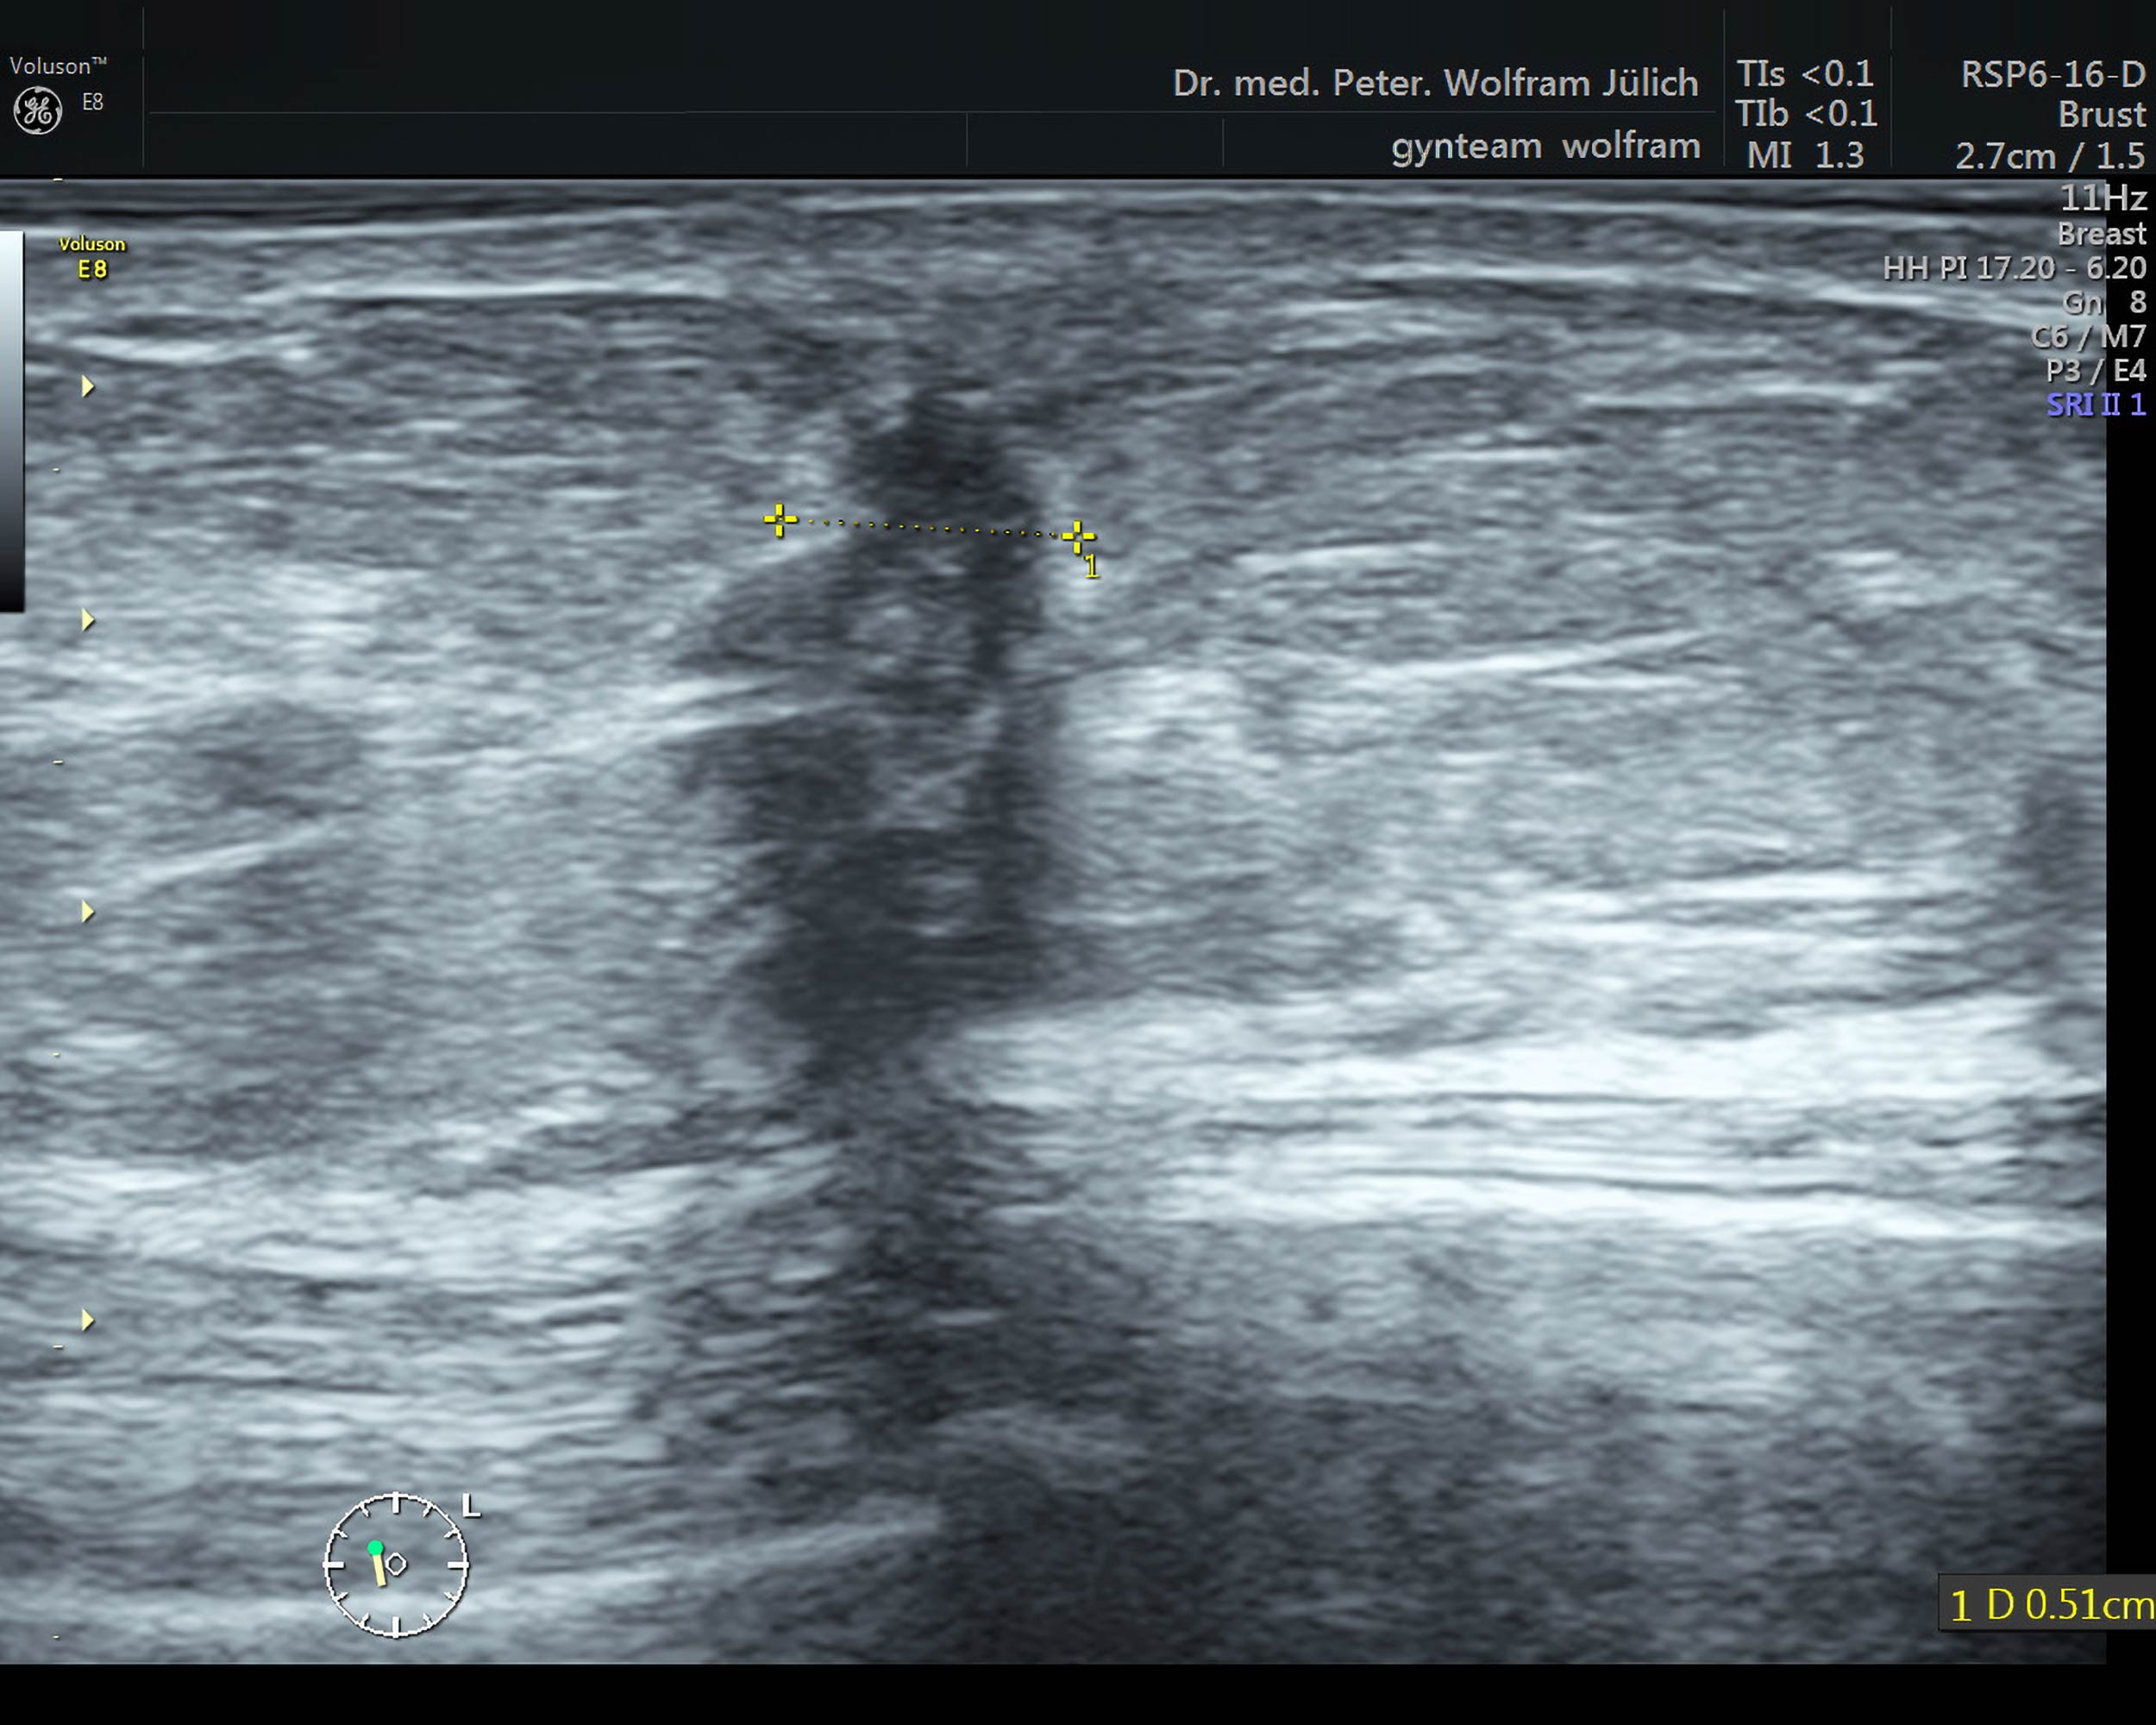

Die Ultraschalltechnologie hat sich in den vergangenen Jahren rasant weiterentwickelt. Die Detailauflösung der neuesten Geräte hat sich in den letzten drei Jahrzehnten in etwa verdreifacht.

In unseren Praxisräumen nutzen wir ein hochmodernes Ultraschallgerät der neuesten Generation der Voluson-Serie. Es bietet neben einem ultrahochauflösenden Schallkopf  folgende zusätzliche Techniken an::

Die Tastuntersuchung der Brust ist angesichts der heute zur Verfügung stehenden bildgebenden Verfahren zu ungenau: Ein Tumor hat zum Zeitpunkt der Tastbarkeit meist schon eine Größe von 2cm und darüber- das erfüllt nicht den Anspruch der Früherkennung. Mit modernen Ultraschallgerätengeräten lassen sich Tumore bereits ab 2mm darstellen.